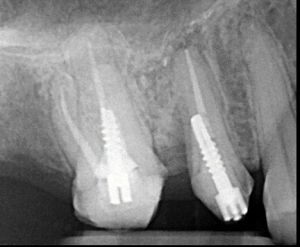

Clinical Cases